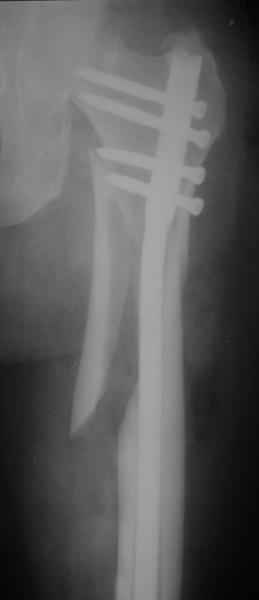

Картинка красивая, но на мой взгляд, не совсем оптимальная: Слишком медиально введён стержень - риск аваскулярного некроза головки бедра.

вариант межфрагментарного шинирования - зона достаточно простительная т.е. чрезвертельные переломы потенциально хорошо срастаются при любом

расположении сопредельных отломков- хорошая локальная васкуляризация. В приведённом случае я бы предпочёл принцип межфрагментарной компрессии (рекон/гамма нэйл 130- 135) принципу шинирования перелома.

Поясни, пожалуйста, почему решил шинировать косой чрезвертельный перелом?

Женя, эта картинка показывает не оптимальное лечение вертельных переломов в моем представлении, а особенности дизайна упомяутого фиксатора.

В частности, его возможности при фиксации переломов проксимального отдела бедра - в сравнении с другими, имеюшими лишь по одному статическому и динамическому отверстию и с кондуктором для введения 2 винтов.

Это было года 2,5 назад, мы тогда еще уточняли возможности шинирования с угловой стабильностью гвоздем с поперечным расположением винтов при переломах проксимального отдела бедра. Пациенту не пришлось приобретать намного более дорогой рекон или проксимальный гвоздь. В приложении еще несколько примеров применения того гвоздя при высоких переломах бедра, в том числе с более латеральной точкой входа. Гвоздь изгибаем для этого.